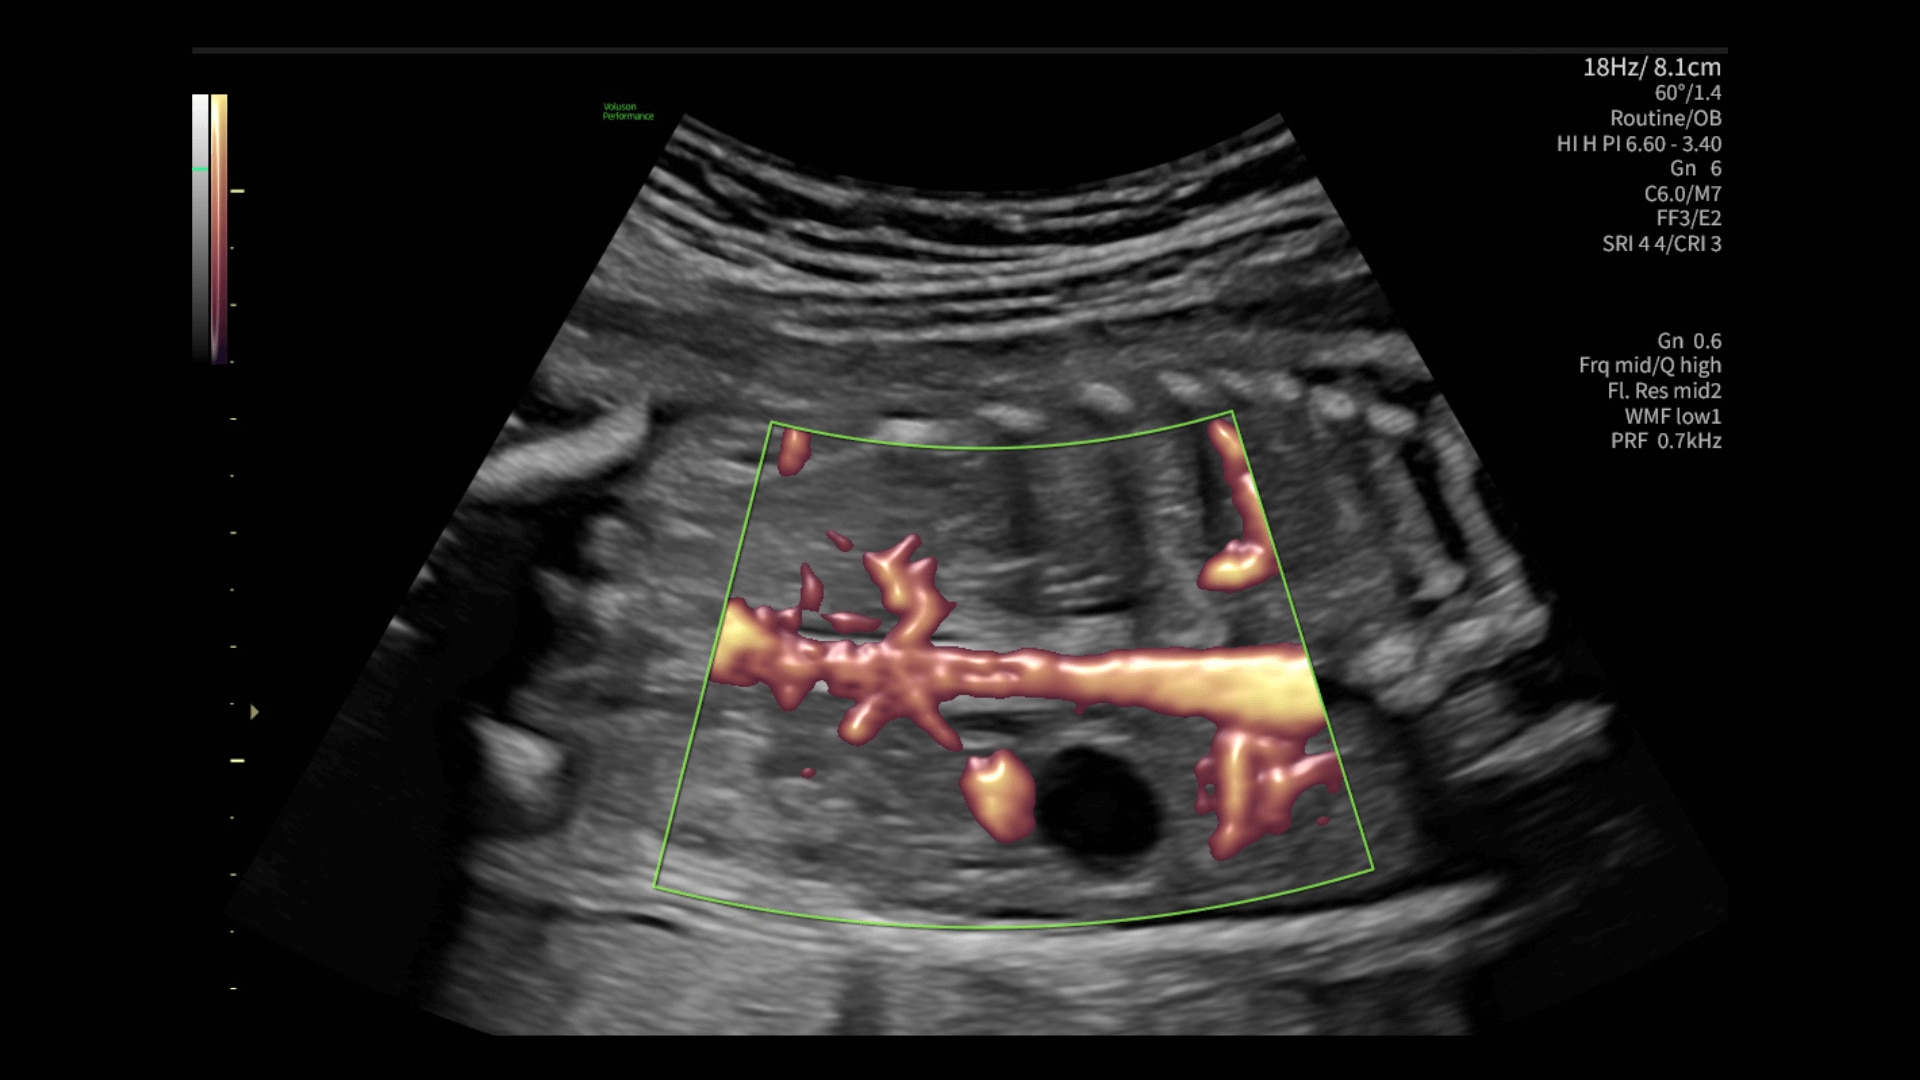

Radiantflow™

Fast, easy 3D-like blood flow visualization

Radiantflow delivers exceptionally sensitive, next level color Doppler for easy fast visualization of blood flow revealing even the tiniest vessels.